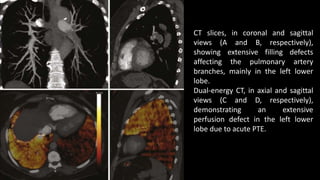

CT slices, in coronal and sagittal

views (A and B, respectively),

showing extensive filling defects

affecting the pulmonary artery

branches, mainly in the left lower

lobe.

Dual-energy CT, in axial and sagittal

views (C and D, respectively),

demonstrating an extensive

perfusion defect in the left lower

lobe due to acute PTE.